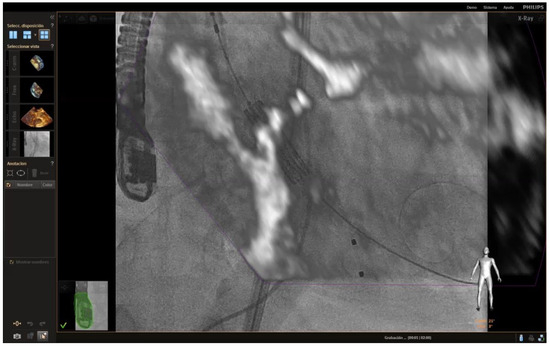

| 2 | TEE monitoring during TAVR implantation allows us to properly position the valve in the aortic annulus, avoiding positioning errors and possible migrations of the prosthesis. |

| 6 | The combination of the new microprobes and the new fusion techniques, which allow the fluoroscopy and the echocardiogram image to be seen simultaneously, will provide the opportunity to do the procedures much faster and more safely for the patient. |